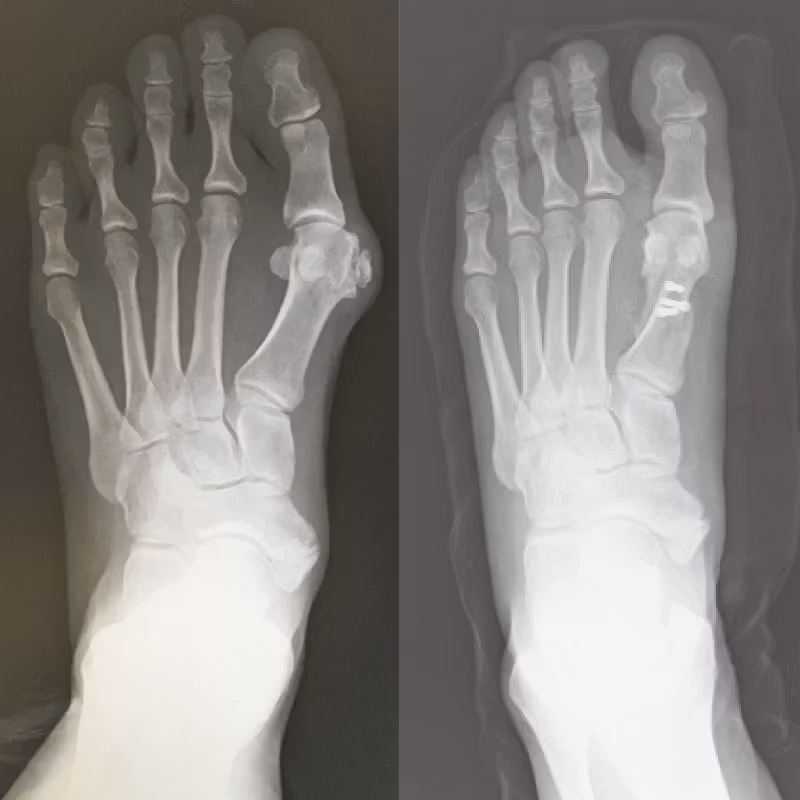

[外反母趾 水平骨切り術]